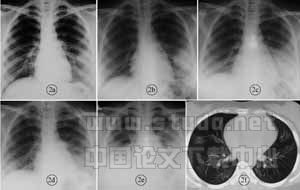

图2 女,24岁,发病第5天X线胸片可见左中外带斑片渗出影(a)。发病第7天病变增大,密度增高,形成团块状实变影(b)。发病第9天到达极期,两肺中下野毛玻璃影(c)。发病第12天病变部分吸收(d)。发病第15天胸片病变再次加重,形成第2峰,心影增大,双侧肋膈角消失(e)。发病第30天胸片正常,CT 片仍可见散在间质改变(f)

通过观察86例SARS患者从初期到极期这个阶段的胸片的动态改变显示:初期、极期均以渗出病变为主。尸体解剖的研究已经证实,SARS患者的肺泡上皮细胞、内皮细胞均为SARS病毒的靶细胞,肺泡毛细血管屏障存在破坏,导致通透性增加,肺泡内大量渗出水肿液而细胞成分很少。随着病程的进展,渗出的增多或吸收,导致胸片动态改变的易变性。早期病灶范围小,密度较低,以后病变增大,密度可以增高。多数患者在8~14天到达病程极期,极期时变化快,病变迅速增大48h超过50%,从单一斑片影变为大片的、多片的肺实质浸润影,从单侧为双侧,部分患者病变呈游走性改变。本文所见病变大多分布于中下肺野,占84.9%(73/86)。大多数患者可形成两肺中下野弥漫的毛玻璃样渗出影,危重患者常表现为ARDS(图2)。极期持续时间一般为4~7天。如患者抵抗力强,治疗及时有效,极期过后2~3天病变开始明显吸收进入病程缓解期。本组病例中9例(10.5%)在病程中X线胸片提示有胸膜渗出(图2、图3),与香港学者《138例SARS病人报告》/[3/]有差异。本组1例患者于病程的极期行胸部CT检查,见两肺广泛的大片状毛玻璃样模糊影,同时可见许多散在的小片状模糊影,另外还见双侧胸腔少量积液,这些在当天的X线胸片中均未显示(图3),如果所有病例均行胸部CT检查,可能会发现更多的双侧病变及胸膜渗出。

在本组病例中28例(32.6%)随着病程的进展,均有不同程度的心影改变(图2),此征象提示SARS的病毒可能同时也侵及心脏,造成心肌损害。

SARS患者在恢复期还要注意有无二重感染的问题,我院病例中有4例(4.7%)患者在恢复期(病程30天)以后,X线胸片再次出现异常改变,且逐渐加重,但患者的临床缺氧症状并不明显,后临床证实为二重感染。由于SARS对人体的免疫损害较大,加之治疗中大量糖皮质激素的使用,机体的反应能力很低,因此要特别注意有无继发二重感染,患者临床感染症状常不明显,而X线胸片已有明显改变。绝大部分极期的病例使用了糖皮质激素,激素使用剂量不尽相同,危重患者均给予大剂量冲击治疗。使用激素治疗体温改变最为明显,胸片动态改变差异并不显著。另外,本组有8例患者(9.3%)在病变已吸收后的2~7天中,症状加重,X线胸片异常改变再次加重,有学者称之为第2峰,这也是SARS胸部影像改变的另一特征(图2)。这种变化机制目前尚不清楚[6]。

本组病变吸收时间为15~21天(51.39%)。此时为病程的缓解期,此后病程逐渐向恢复期演变。大多数患者胸部X线检查已无异常发现,部分患者残留阴影吸收较慢,特别是行胸部CT扫描,发现肺部间质性改变者甚多。本组病例中有23例在恢复期同时行CT扫描,无极期表现的4例中,于发病的第4~7周复查X线胸片均无异常,CT扫描有2例仍可见局限性细网状影。有极期表现的19例中,于发病第5~8周复查16例,其中仍有12例胸部CT片可见散在的、程度不同的间质性改变,而同期胸片仅有4例表现异常。另有3例胸片无异常的患者于发病8周以后复查,有2例CT扫描正常,1例仍可见间质性改变。这些结果表明,SARS患者恢复期肺内间质性改变普遍存在,不容忽视。本组中间质性改变的比例甚高,可能由于大多数复查病例为在院住院时间较长,病情较重所致。但从研究结果表明,恢复期患者行胸部CT检查是必要的。